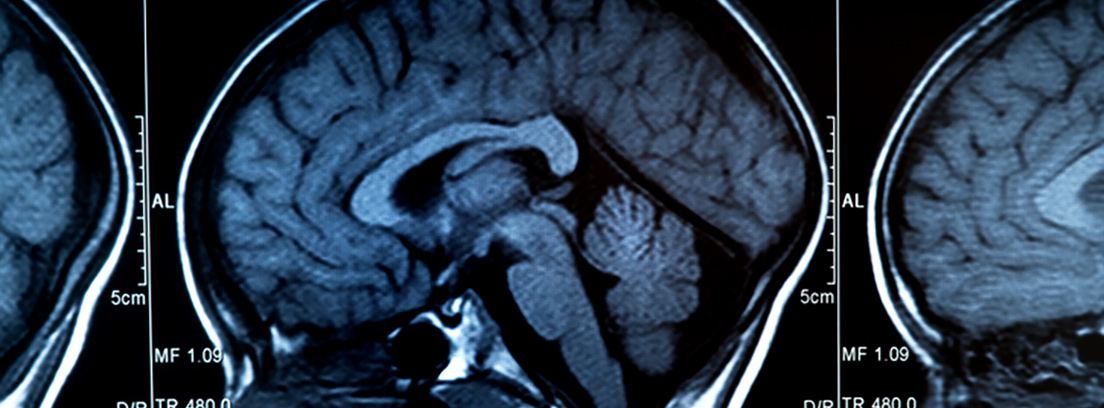

La prueba de imagen principal que detecta el 100% de las hemorragias intraparenquimatosas y el 95% de las hemorragias subaracnoideas es el TAC craneal. Asimismo se podrán descartar causas secundarias de hemorragias, como las malformaciones arteriovenosas, cuyo diagnóstico debe evaluarse con rapidez por su potencial tratamiento quirúrgico.